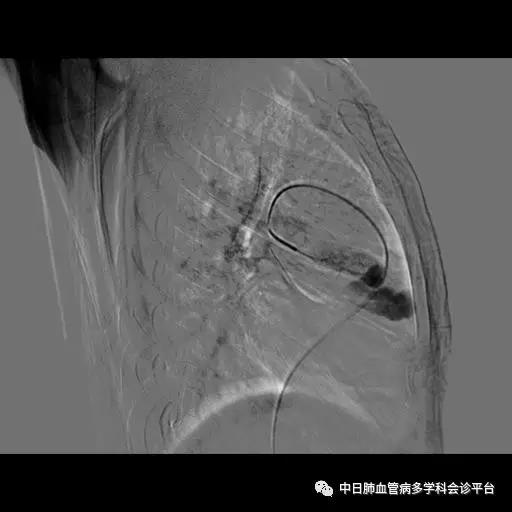

超声心动图及右心声学造影示肺血管水平右向左大量分流。进一步胸部增强CT显示右肺中叶动静畸形并瘤内附壁血栓形成,右侧胸腔积液,右下肺膨胀不全。患者右肺动静脉瘘瘤样扩张血管贴近脏层胸膜,出血原因考虑为右肺动静脉瘘破裂出血。行肺动脉造影可见右肺动脉中叶内侧支(RPA5)动静脉畸形,超选后应用COOK微弹簧圈行右肺动脉中叶内侧支(RPA5)栓塞术。肺动脉栓塞术后复查血常规血色素逐渐上升至94g/L,复查CPTA:主肺动脉及各叶段肺动脉未见明确肺栓塞征象;右肺中叶AVM术后,瘤体闭塞,内侧段肺梗死灶;右侧胸腔积液较前明显减少,右下肺膨胀不全。

胸部增强CT:右肺中叶动静畸形并瘤内附壁血栓形成,右侧胸腔积液,右下肺膨胀不全。